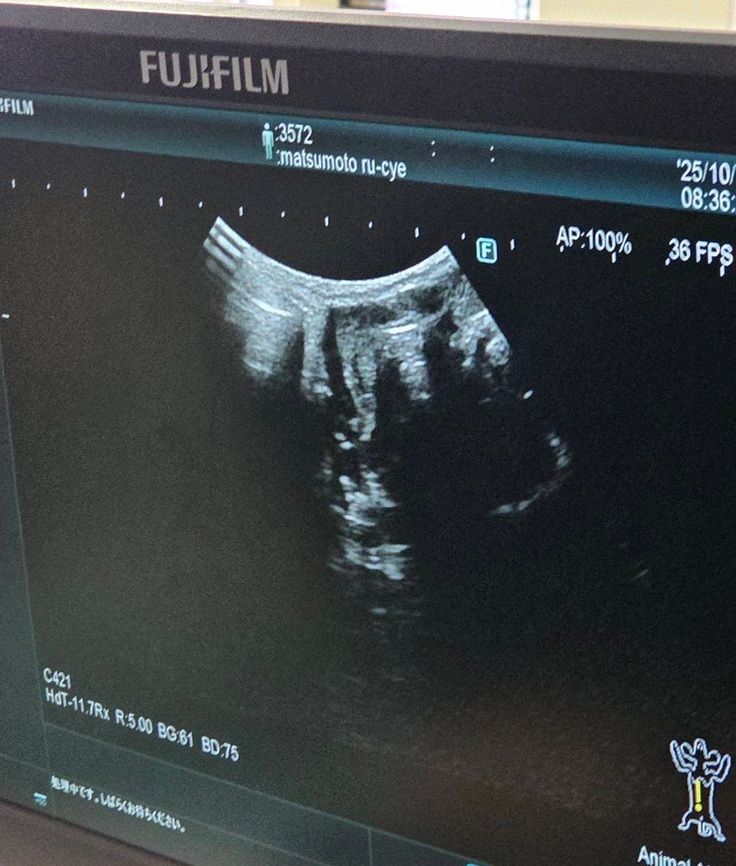

血液検査の写真は撮れなかったのですが、エコー検査では

↓腎臓転移なし

↓肝臓転移なし

↓膀胱転移なし

↓反対側の腎臓も転移なし

↓左目腫瘍なし

↓喉腫瘍なし

※正面から撮りたかったのですが先生がいたので撮れず、見づらくて申し訳ないです。